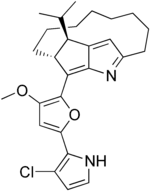

| IUPAC name

| C27H33ClN2O2 | |

| Molar mass | 453.02 g/mol |

Roseophilin is an antibiotic isolated from Streptomyces griseoviridis shown to have antitumor activity.[1] The chemical structure can be considered in terms of two components, a macrotricyclic segment and a heterocyclic side-chain. Several laboratory syntheses of roseophilin (e.g., those of Trost, Fürstner, Salamone) are based upon the Paal-Knorr synthesis, and two others are based on the Nazarov cyclization reaction (those of Tius, Frontier). The compound is related to the prodiginines.[2]